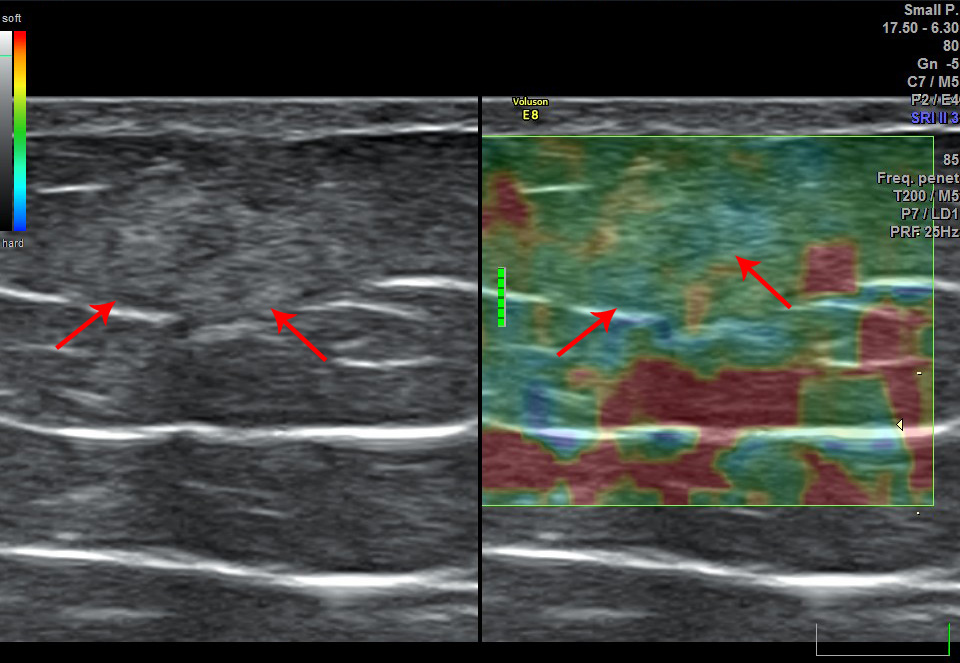

При ультрасонографии мест инъекций липогипертрофии выявлены у 80 (98%) пациентами, включая 25 с СД1 и 55 – с СД2. Cуммарная площадь участков липогипертрофий на передней брюшной стенке варьировала от 50 до 1847 мм2 (медиана 370 мм2). В большинстве случаев (91,5%) участки липогипертрофии характеризовались повышением эхогенности относительно неизмененной ПЖК (рис. 1). Медианы показателей MG1 и MG2 составили 37,8 и 29 соответственно, p<0,001. При исследовании в режиме компрессионной соноэластографии участки гипертрофии, как правило, демонстрировали большую жесткость по сравнению с неизмененной клетчаткой, при этом наблюдалось гетерогенное увеличение жесткости большинства образований (рис. 2). В режиме 3D-ангио обнаруживались гиповаскулярные зоны в области участков липогипертрофии (рис. 3), что подтверждалось при количественной оценке параметров кровотока (рис. 4).

Рис. 2. Гетерогенный участок липогипертрофии повышенной жесткости в подкожной клетчатке передней брюшной стенки у больного сахарным диабетом. Слева: серошкальное сканирование в B-режиме, справа: компрессионная соноэластография, исследование в режиме реального времени (Real Time Elastography). Синим цветом окрашены участки повышенной жесткости.